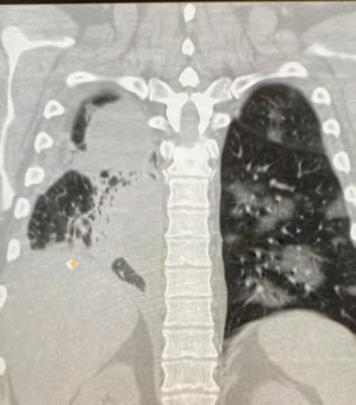

Many calls, however, result in lives being saved, and Marcos has personally been able to keep people alive using his naloxone overdose treatment kit. In October of 2019, he responded to an overdose call for an adult male and used the naloxone kit to keep him alive while waiting for paramedics. Marcos was given a lifesaving award for his actions, as it is believed the man would not have survived otherwise.

Again in February of this year, Marcos expertly administered the overdose treatment, this time to a 2-year-old who had eaten some of his parent’s medication.

“When I arrived to the call, the toddler was coming in and out of consciousness. Based on my training and experience, I knew Percocet to be an opioid derivative and knew that the naloxone treatment could stop or reverse the effects. Also based on the child’s deteriorating condition and knowing the snow was slowing the response time for LifeNet, I administered one dose in the right nostril. A few moments later the child came to, cranky, but otherwise normal.”

Officer Luna received T.A.P.D.’s Lifesaving Award for his efforts on October 15, 2019, while responding to a call. Upon arrival to a residence in College Hill, he observed a white male on the ground. Based on Officer Luna’s training and experience, he knew that the man was overdosing. He administered two doses of naloxone, which more than likely, saved the man’s life.